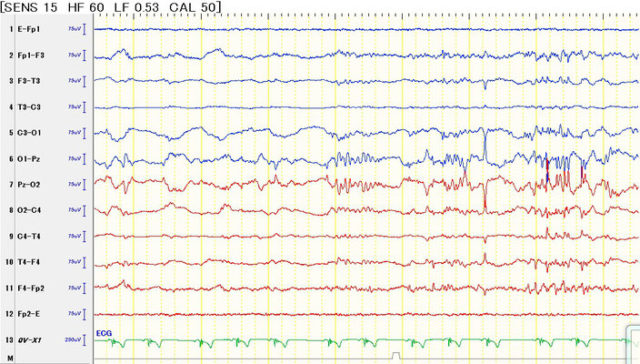

てんかん(Epilepsy)

特発性てんかん

てんかんは大脳神経細胞の過剰な興奮により様々な発作症状を起こす疾患です。

問診

血液検査

尿検査

心電図検査・血圧測定

CSF検査

などを行い除外診断しつつ、脳波検査によるてんかん性異常脳波の検出をを行うことで診断します。